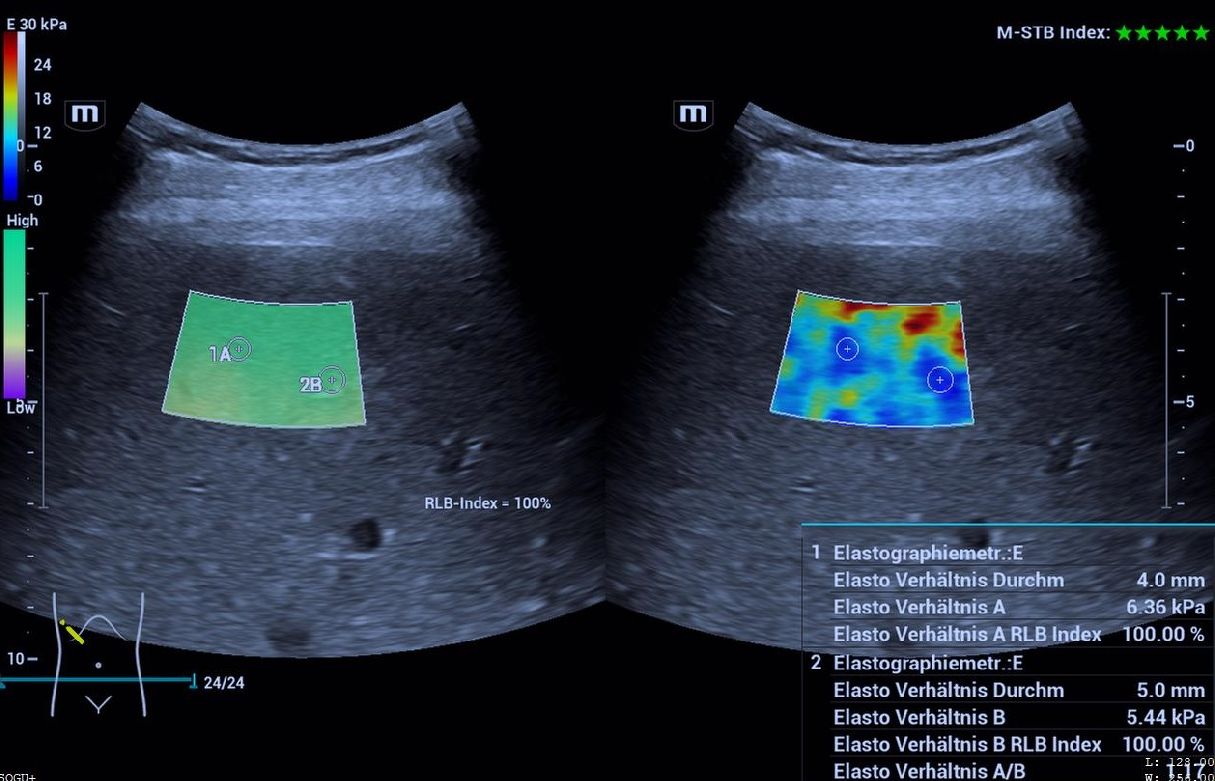

Scherwellenelastographie

Die Scherwellenelastographie ist ein recht neues Ultraschallverfahren zur Darstellung von Dichteunterschieden in Organen. Schon länger wird es bei der Fragestellung der Fettleber genutzt und ist hier etabliert ("Fibroscan").

Zunehmend gewinnt es auch in anderen Bereichen an Relevanz dazu, so z.B. zur genaueren Beurteilung von Schilddrüsenknoten oder Sportverletzungen im Bereich der Sehnen und Muskulatur.

Wir haben die Scherwellenelastographie schon lange im Blick und so war es nur konsequent, dass unser neues Ultraschallgerät diese Technik auch beherrscht.

Wir freuen uns somit, dass wir ihnen als einzige Praxis „weit und breit“ nun dieses moderne Verfahren anbieten zu können.

Aktuell wird die Scherwellenelastographie nur von Dr. Rathje durchgeführt. Sie ist seit Neuestem auch Bestandteil der Gesundheitsuntersuchung plus zur besseren Beurteilung der Leber.

Uns 4 Ärzten haben 2 Unterschallgeräte nicht ausgereicht. Es war daher zu Beginn des Jahres klar, dass ein drittes, neues Gerät angeschafft werden muss. Nun ist dieses Gerät der letzten Ultraschallgeneration geliefert worden und wir sind begeistet. Die Bildqualität ist wieder verbessert worden, nicht nur wegen der speziellen Ultraschallköpfe, die u.a. noch genauere Untersuchungen der Gelenke, Sehnen aber auch der inneren Organe zulassen. Desweiteren können wir mit diesem Gerät nun neu Herzultraschalluntersuchungen (Echokardiographien) und auch sonographische Gewebedichteanalysen (mittels Scherwellenelastographie) durchführen, was z.B. für chronische Sehnenprobleme wie dem Tennisellenbogen aber auch für die Fettleber und deren mögliche Komplikationen eine sehr wichtige Zusatzinformation darstellt. Letzte beide Untersuchungen führen wir ausschließlich im Rahmen spezieller Vorsorgeuntersuchungen (GU+, Sportcheck, Schlaganfallcheck) durch.